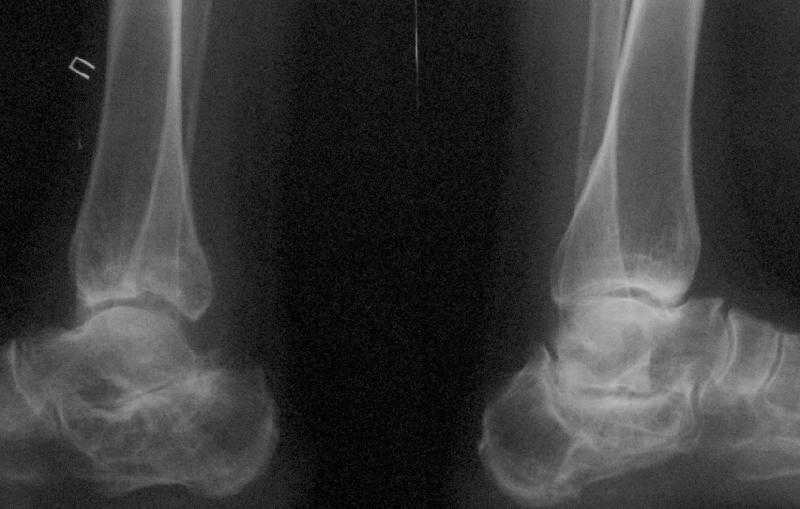

Уважаемые коллеги! Помогите определится с тактикой лечения.Оскольчатый импрессионный перелом заднего края правой большеберцовой (Пилон?) кости 5-ти недельной давности на фоне неправильно сросшихся переломов пяточных костей (травма в 1991г.), ДОА подтаранных суставов 3 ст. До последней травмы больная ходила без особых проблем и работала пекарем (работа на ногах).Суть проблемы в том, что открытая анатомическая репозиция в таком сроке представляется мне крайне травматичной, что может привести к неблагоприятному функциональному исходу.Варианты решения:1) оставить "как есть" с последующим артродезом после развития ДОА2) выполнить остеотомию и попытаться низвести основную часть суставной поверхности3) выполнить попытку анатомической репозиции из задне-латерального??? доступа.

По снимкам довольно сохранный сустав, и такой сустав желательно попытаться восстановить всеми возможными мерами.

Насчет пилона, прошло достаточное время для консолидации и прекрасная возможность для демонстрации, что такие случаи могут быть успешно вылечены остеотомией, несмотря на засторелость.